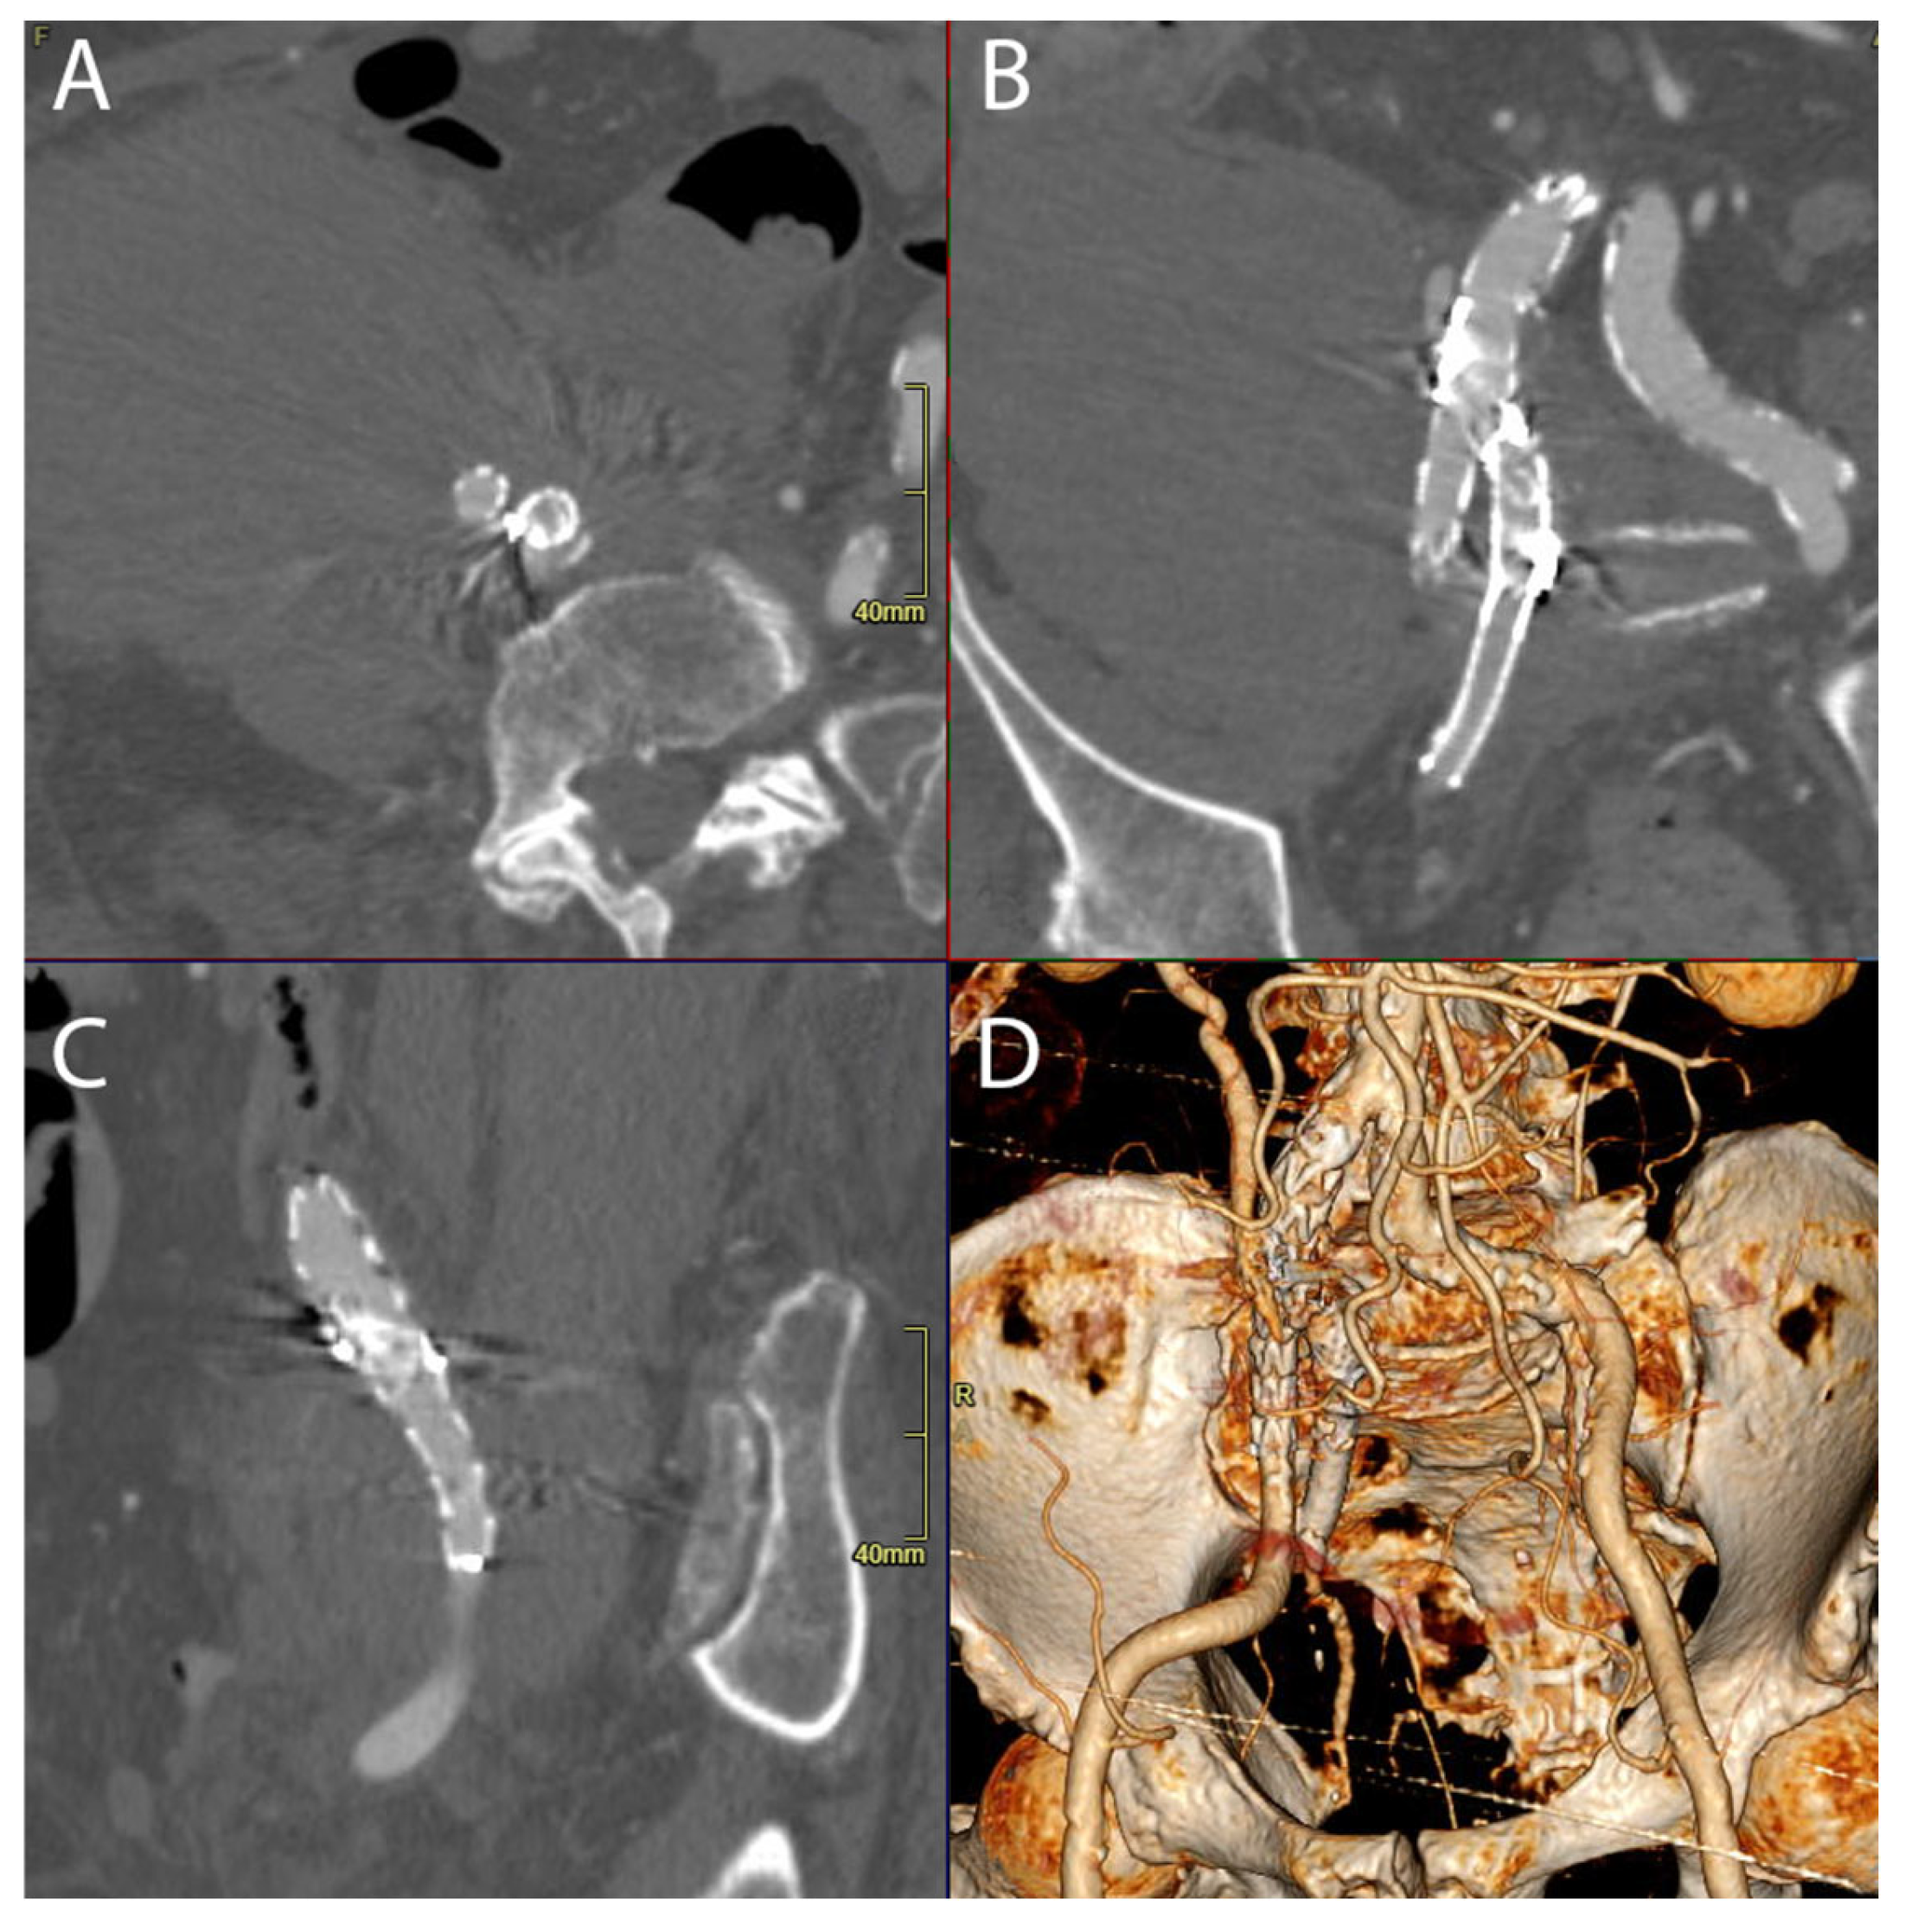

This intervention successfully managed the recurrent rupture, and the patient achieved clinical stability, leading to their discharge on the 35th postoperative day. Se Figure 3.

Figure 3. Multiplanar reformation (MPR view in axial (A), coronal (B), sagittal (C)) and 3D reconstruction (D) of postoperative CT angiography demonstrating that the endograft (Endurant II limb) extends to cover the common and external iliac arteries, along with embolization of the right internal iliac artery.